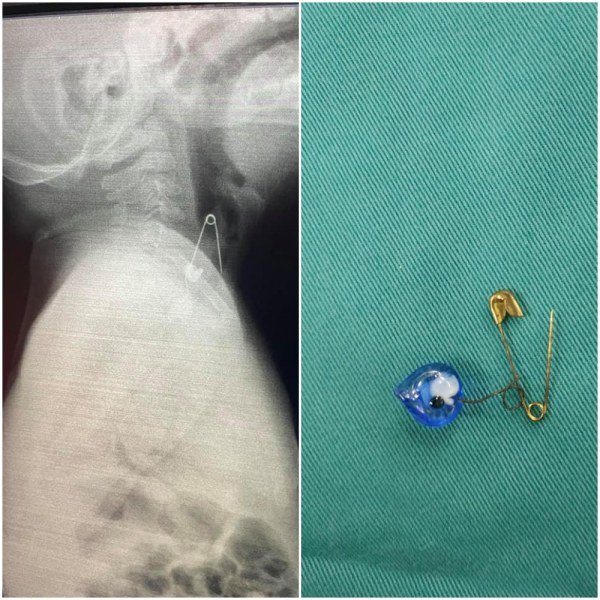

Точно това се е случило във Варна, където лекари извадиха отворена безопасна игла в ларинкса на 6-месечно бебе, а родителите му изживяха истински ужас.

Звучи страшно, а и изглежда страшно. Хубавото е, че благодарение на професионализма на специалистите от УМБАЛ „Св. Марина“ и детския хирург Георги Иванов бебето вече е отървано от синьото око с безопасна игла, а с него – и от уроките.